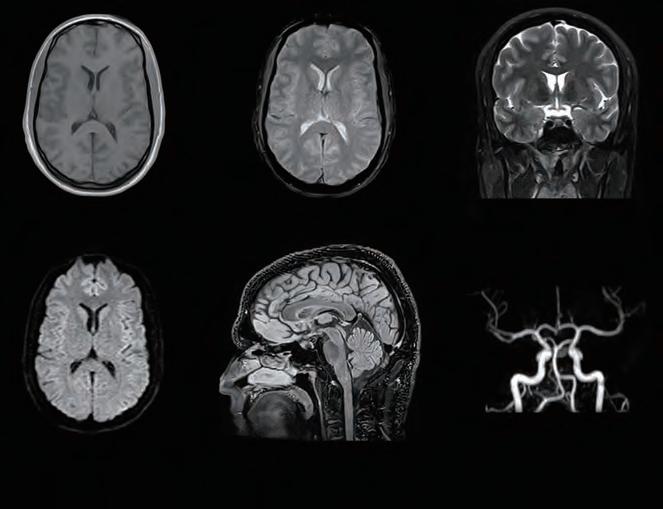

By using ultrasound, CT or MRI, we can see the extent of commonly occurring (Fig 2) or unique injury on site within our dedicated Medical Imaging Centre4 at the Manchester United Carrington Training Centre without any of the confidentiality issues of transferring a patient to a local hospital. Figure 3, for example, shows a T2 weighted image of the coronal view of the right knee showing an acute pivot shift injury with an acute lateral condylar bony contusion which is highly indicative of an associated ACL tear. The female athlete was examined using a Canon Medical Vantage Galan 3T MRI.

Top Right

Fig 2: Canon Medical Vantage Galan 3T MRI acquired Axial PD Fat Supressed image of the right ankle demonstrating a grade 1/2 tear of the anterior talofibular ligament (ATFL).

Bottom Right

Fig 3: Coronal PD Fat Saturated image of the right knee showing an acute pivot shift injury with an acute lateral condylar bony contusion, which is highly indicative of an associated anterior cruciate ligament (ACL) tear acquired using Canon Medical Vantage Galan 3T MRI.